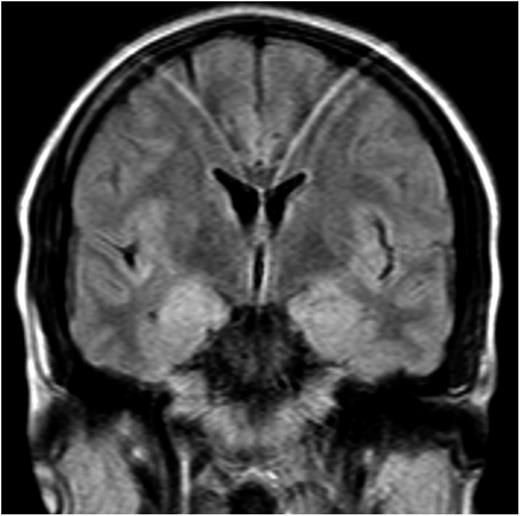

Patients with LE develop short-term memory loss or amnesia, disorientation, confusion, depression, anxiety, or frank psychosis with visual or auditory hallucinations or paranoid ideation. Generalized or partial complex seizures occur in ∼50% of the patients. HL is the third most common cause of LE after SCLC and testicular germ cell tumors.18 The cases reported in the English literature are summarized in Table 3.16,18-29 The association of LE with HL is also known as Ophelia syndrome.19 The clinical and magnetic resonance imaging (MRI) features (Figure 2) are not different from those reported in LE associated with other tumors. However, the LE of patients with HL has a better prognosis; frequently, successful treatment of the tumor is sufficient to result in full neurological recovery. This is probably related to the finding that this type of LE occurs in association with an antibody against the mGluR5 that probably results in reversible neuronal dysfunction rather than neuronal death (Figure 3).16,30

Coronal T2-weighted MRI scan of a patient with LE, mGluR5 antibodies, and HL. There is increased T2 signal of the head of both hippocampi. Study is slightly affected by motion artifact.